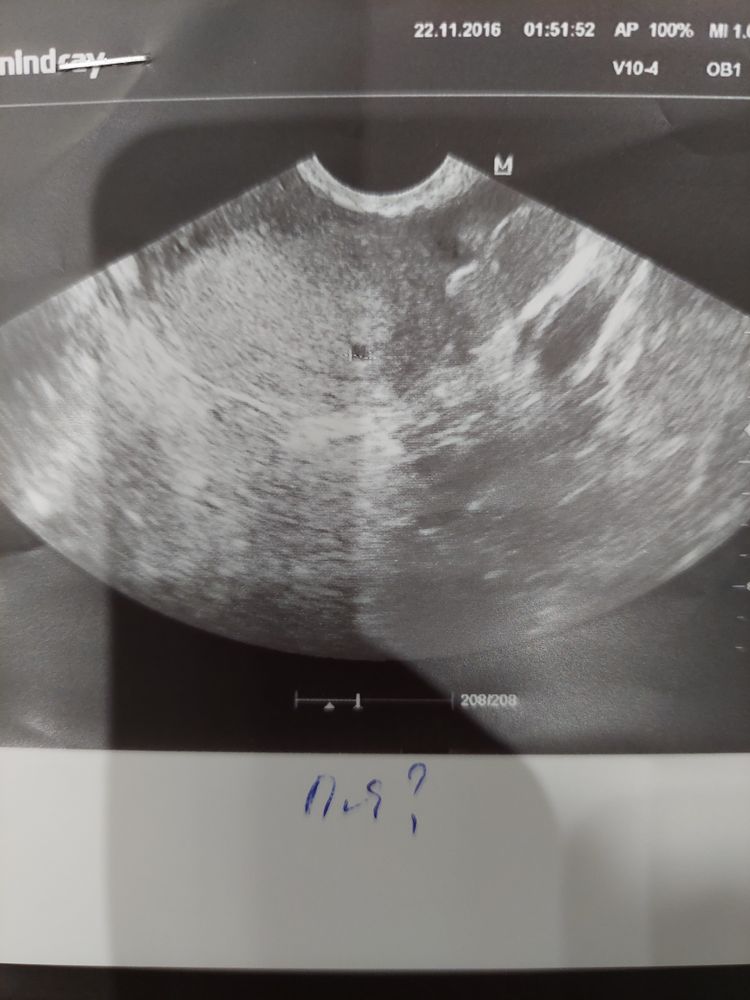

Мама двоих (8 лет, 1 год) Нижний Новгород

Изображение Наталья Волгунова, вот моё, мне кажется очень похоже, только у вас может на пол миллиметра поменьше.

Оленька, да похоже

Наталья Волгунова, я конечно не врач, но при таком хгч я бы сказала что это ПЯ. Сходите на узи еще в другое место, где аппарат получше